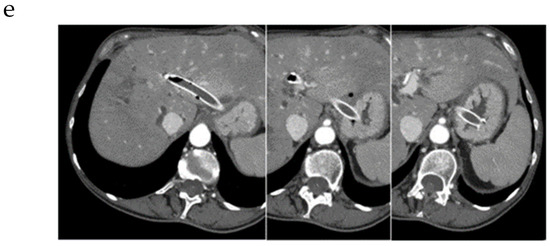

3.1.1. EUS-BD of the Bile Duct

3.1.2. EUS-GBD

5. Rendezvous Techniques

5.1. Should Rendezvous Be Used First?

5.2. Which Rendezvous Route Should Be Used?